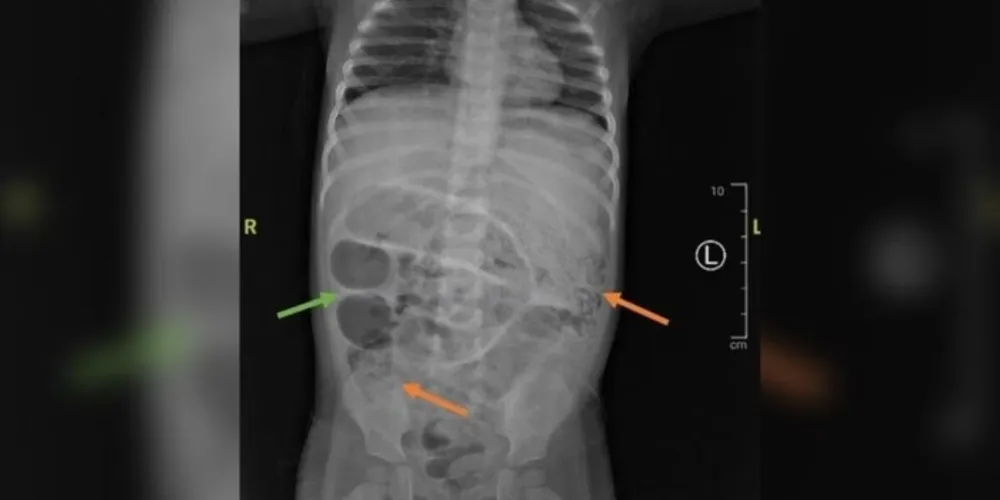

VERMES BLOQUEIAM O INTESTINO DA CRIANÇA - Após os episódios de vômito, os médicos realizaram exames de imagem. A radiografia revelou áreas opacas no intestino, compatíveis com obstrução intestinal. O quadro foi agravado por anemia e leucocitose — o aumento do número de glóbulos brancos no sangue —, indicativos de infecção parasitária.

Durante uma cirurgia de emergência, os médicos encontraram três pontos distintos do intestino delgado completamente bloqueados por vermes.